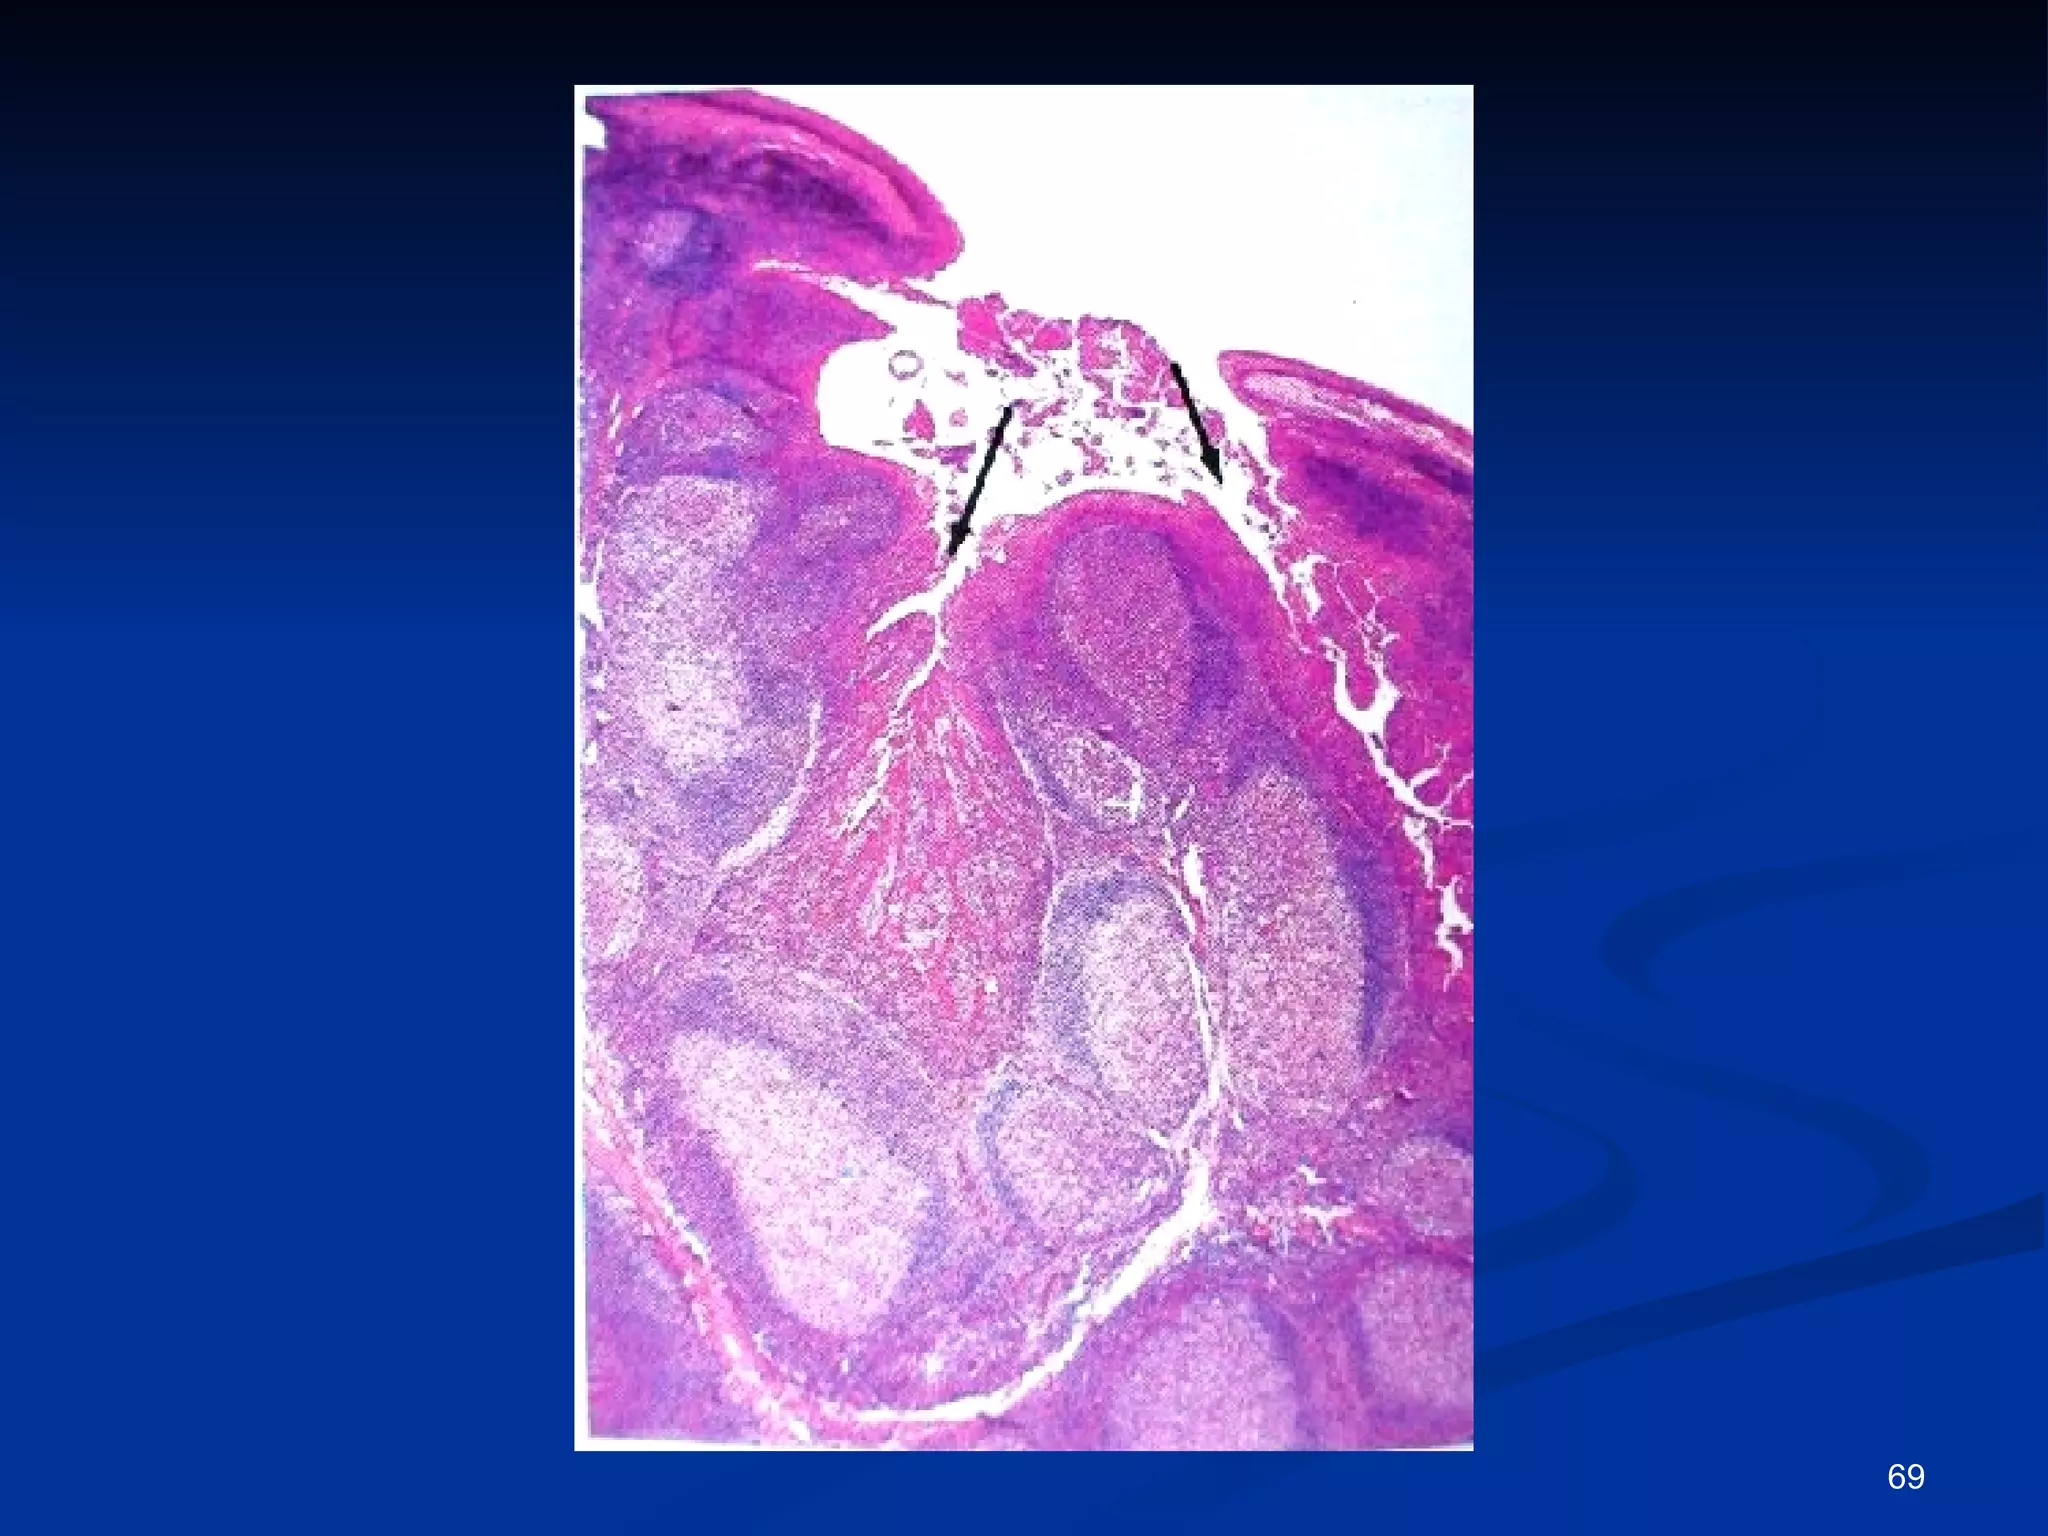

Tonsilas ou  Amídalas   Palatinas Faríngeas  Linguais Agregados encapsulados incompletos de nódulos linfóides que protegem a entrada da orofaringe Estão interpostas no caminho dos Ag aspirados e ingeridos Reagem aos Ag formando linfócitos e montando uma resposta imune

Tonsilas palatinas Bilaterais - localizadas no limite entre a cavidade oral e a orofaringe, entre as pregas palatoglossal e palatofaríngea Recoberta por epitélio estratificado pavimentoso não-queratinizado, que forma 10 a 12 criptas profundas. que se invaginam no parênquima da tonsila - contém células epiteliais descamadas, leucócitos mortos, bactérias e restos de comida Parênquima da tonsila é constituído por numerosos nódulos linfóides, muitos com centros germinativos, indicativos de formação de células B

Tonsilas palatinas Bilaterais- localizadas no limite entre a cavidade oral e a orofaringe, entre as pregas palatoglossal e palatofaríngea Recoberta por epitélio estratificado pavimentoso não-queratinizado, que forma 10 a 12 criptas profundas. que se invaginam no parênquima da tonsila - contém células epiteliais descamadas, leucócitos mortos, bactérias e restos de comida Parênquima da tonsila é constituído por numerosos nódulos linfóides, muitos com centros germinativos, indicativos de formação de células B

Tonsila faríngea  Única - situada no teto da faringe nasal Em vez de criptas, possui pregas longitudinais rasas, chamadas dobras.  Revestida por epitélio pseudo-estratificado cilíndrico ciliado Parênquima constituído de nódulos linfóides, com centros germinativos ocasionais Quando inflamada - adenóide